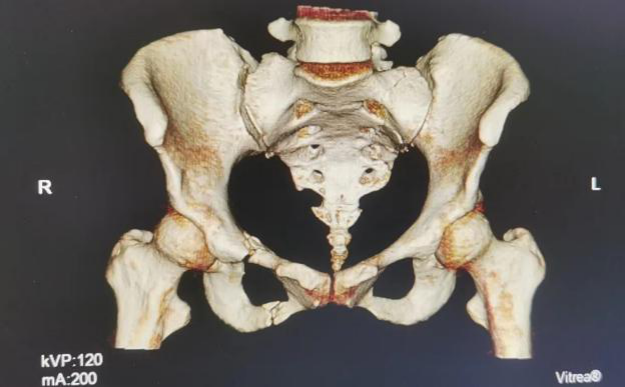

入院后完善了相关检查诊断:多发性骨盆骨折(Tile分型C 3型)、腰椎骨折、肺挫伤、创伤性胸腔积液。

术前三维